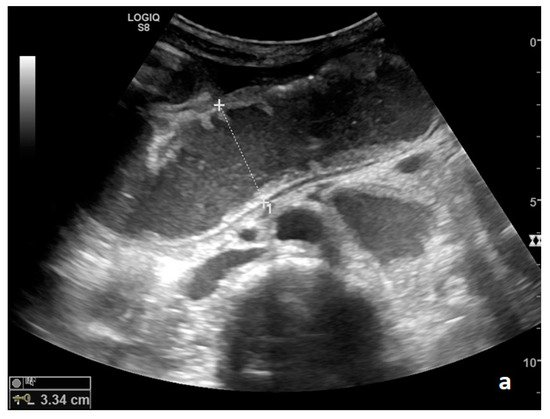

Parietal changes are characterized by the presence or absence of parietal and valvulae conniventes thickening and parietal wall stratification. The evaluation of parietal changes follows a dichotomic diagnostic process based on the reference values (normal thickness 1–3 mm, wall thickening >3 mm, thinned walls <1 mm): thickened walls/valvulae conniventes (YES/NO) or thinned walls (YES/NO) [11][12][3]. Although ultrasound allows us to identify the five concentric layers of the intestinal loops, this evaluation is not applied in the diagnosis of SBO. In practice, the evaluation is limited to the presence or absence of parietal stratification (two-layer double halo sign or three-layer target sign) (Figure 4a–d and Figure 5a,b) [11][3][13].

Figure 4. A complicated SBO in a 69-year-old male with gastric cancer and peritoneal carcinosis. Ultrasound images show long (a) and axial (b) evaluations of a fluid-filled, dilated small bowel loop with hyperechogenic floating material (shown with an asterisk) (b,d). Bowel peristalsis was absent. Mild parietal and valvulae conniventes thickening are present (c,d). Downstream loops present normal caliber (bowel jump diameter). Free fluid is interposed between bowel loops (black arrow) (b).

The valvulae conniventes (Kerckring valves, circular folds) are permanent folds composed of mucosa and submucosa that project into the intestinal lumen and are clearly visible in the case of fluid distension (keyboard sign) [5]. At an early stage of SBO, it is not uncommon to see the valvulae in the upstream loop appearing more numerous and closer to each other. As the occlusive state continues, the loop upstream of the obstructive fulcrum becomes weaker, bowel walls appear thin, and the folds flatte. The upstream loops more distant from the obstructive fulcrum may still present peristalsis, albeit reduced and ineffective. In complicated ileus, with the onset of vascular loop distress, the walls and valvulae become thicker and weaker due to parietal edema and venous stasis, with possible dramatic parietal necrosis and subsequent perforation (Figure 4a–d and Figure 5a,b) [2][14].